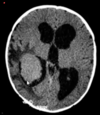

Regarding EPENDYMOMA, remember:

OBSTRUCTIVE COMMUNICATING HYDROCEPHALUS:

-causes?